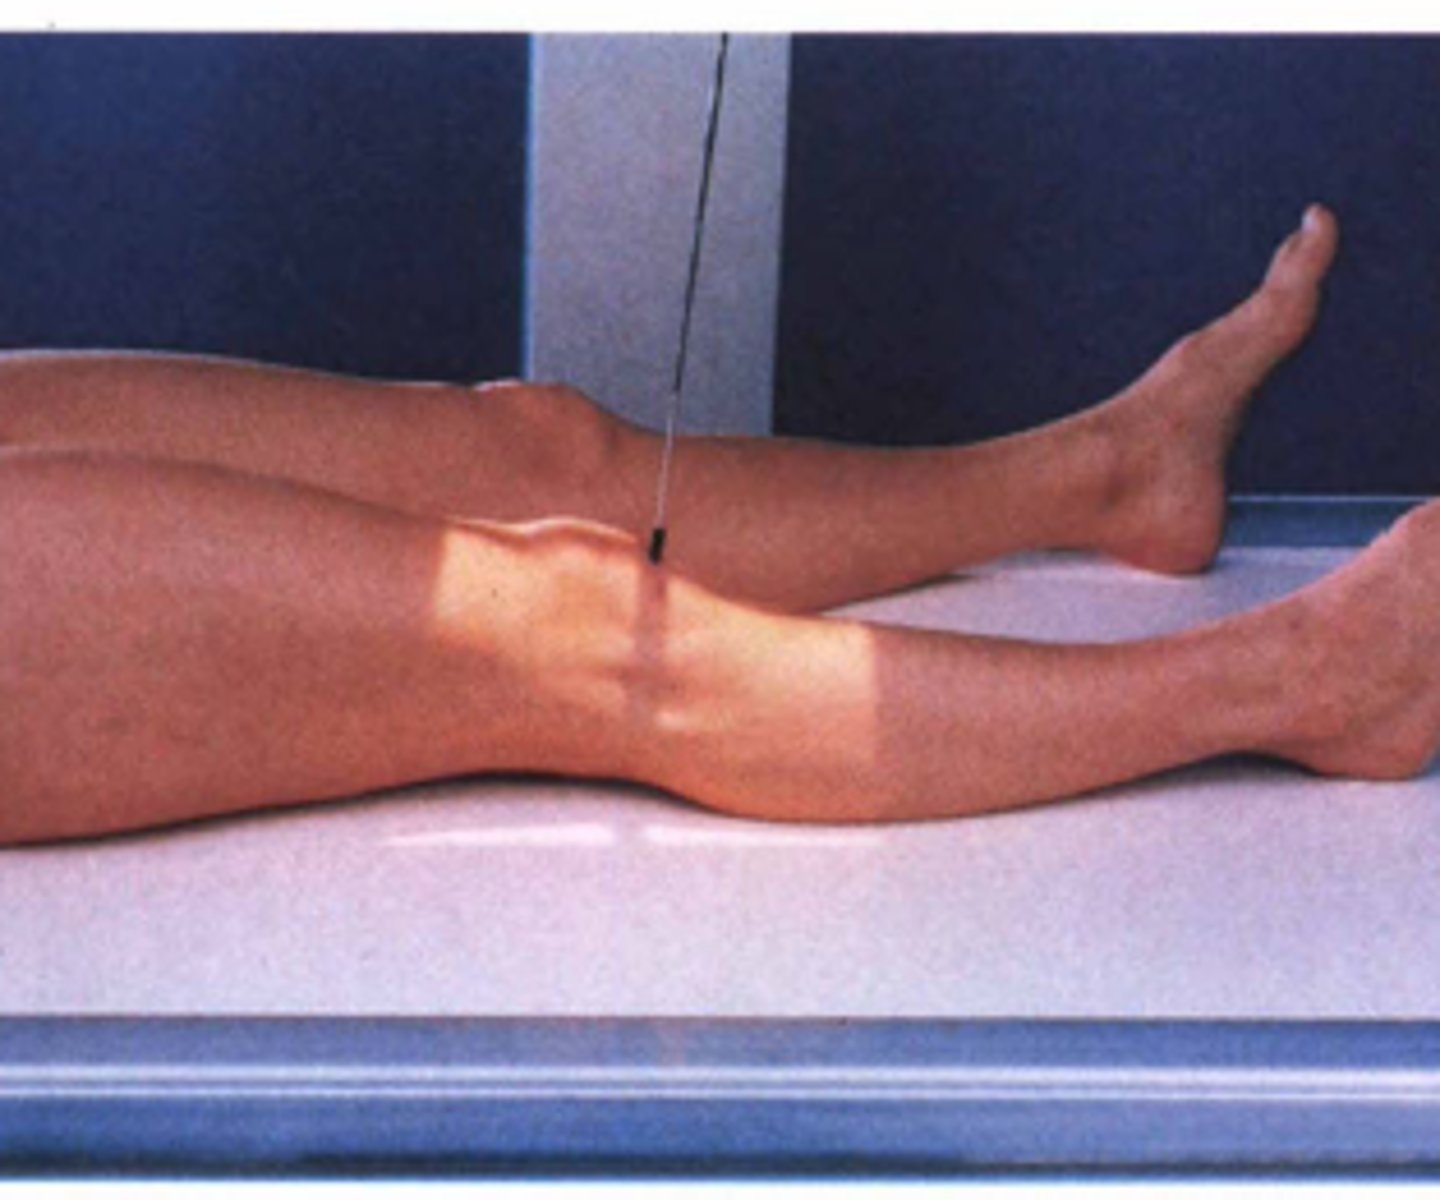

Describe, in detail, the positioning of the PATIENT when doing a supine LATERAL KNEE (non-trauma) (position 1)

1. Patient lies supine on the x-ray couch and turns onto the affected side so that the lateral aspect of the knee is in contact with the IR.

2. The affected knee is flexed through either 45 or 90 degrees and the leg is turned to superimpose the femoral condyles.

3. A small pad should be placed under the ankle joint to ensure the tibia is parallel to the x-ray couch.

Describe, in detail, the positioning of the PATIENT when doing a supine LATERAL KNEE (non-trauma) (position 2)

1. Patient lies on the affected side to be examined and the knee is flexed at either 45 or 90 degrees.

2. The unaffected leg is brought in front of the one being examined.

3. A small pad should be placed under the ankle joint to ensure the tibia is parallel to the x-ray couch.

4. The femoral condyles of the knee being examined should be superimposed.